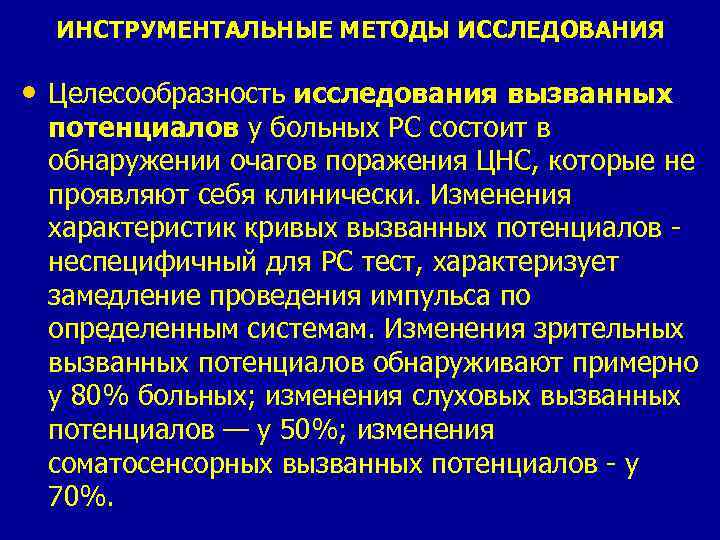

ИНСТРУМЕНТАЛЬНЫЕ МЕТОДЫ ИССЛЕДОВАНИЯ • Целесообразность исследования вызванных потенциалов у больных PC состоит в обнаружении очагов поражения ЦНС, которые не проявляют себя клинически. Изменения характеристик кривых вызванных потенциалов - неспецифичный для PC тест, характеризует замедление проведения импульса по определенным системам. Изменения зрительных вызванных потенциалов обнаруживают примерно у 80% больных; изменения слуховых вызванных потенциалов — у 50%; изменения соматосенсорных вызванных потенциалов - у 70%.